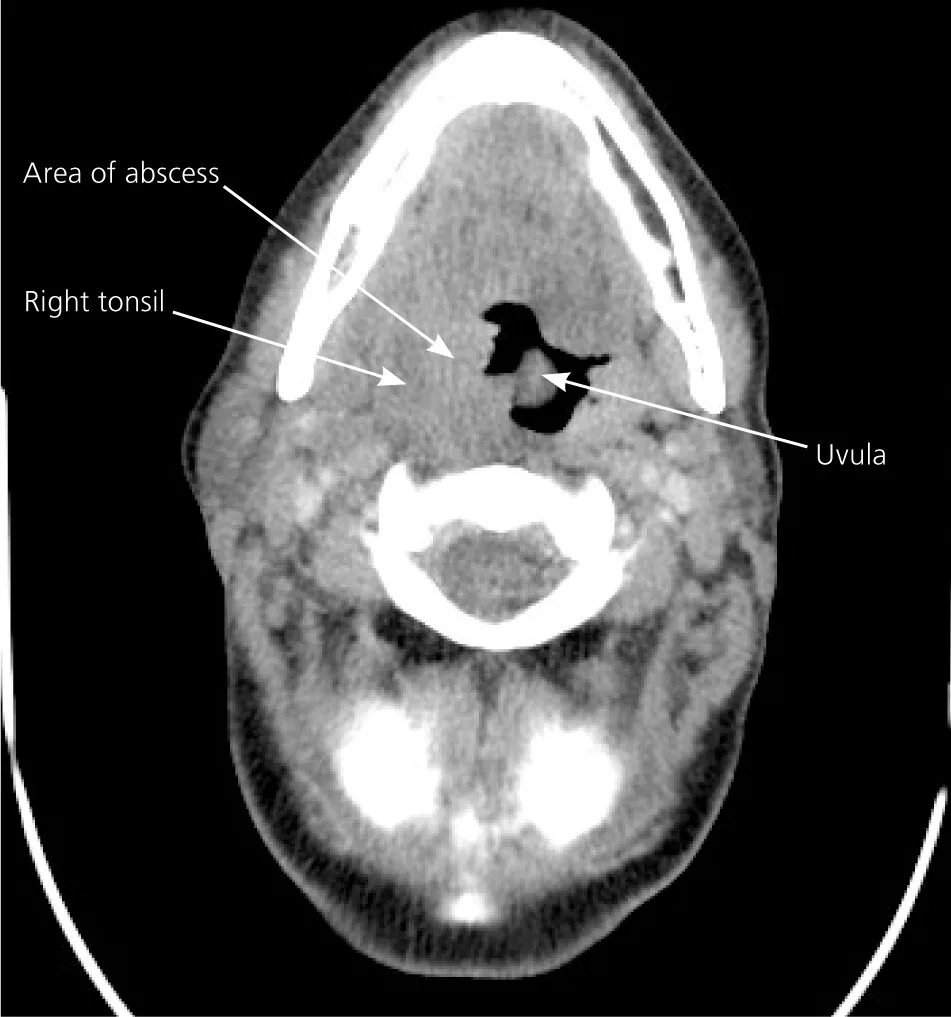

Миндалины на кт